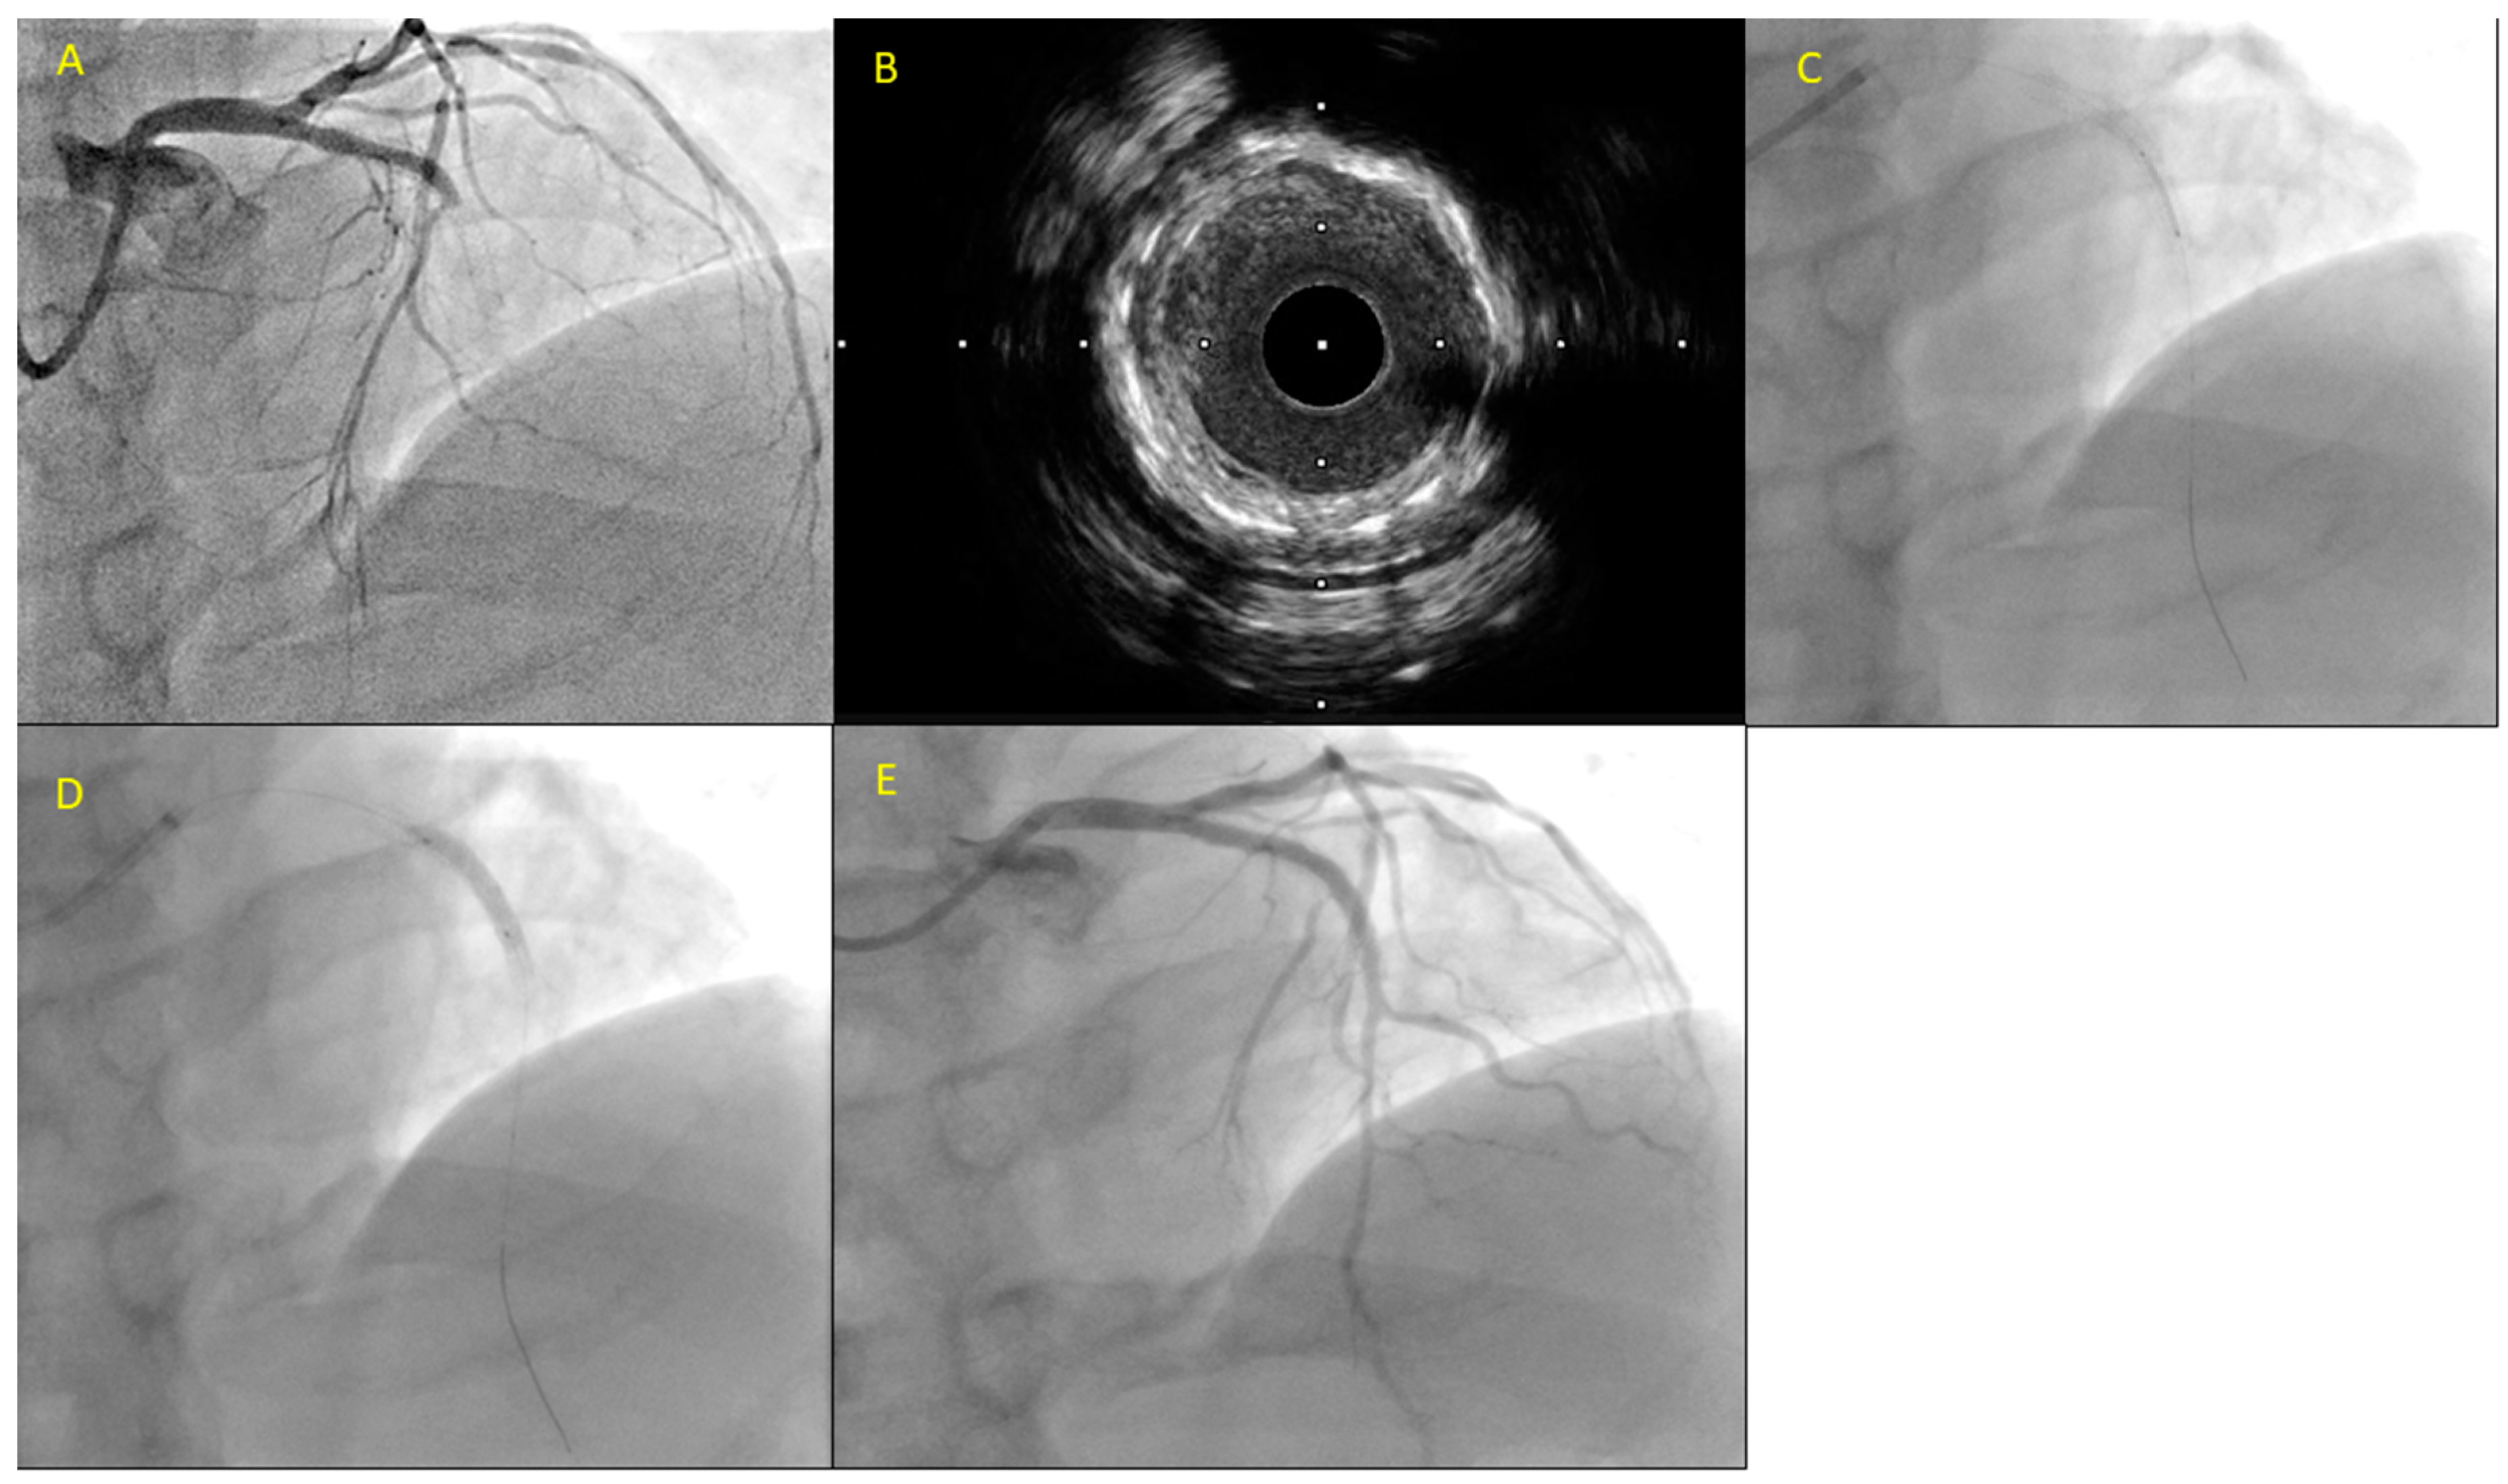

Figure 2.

A fifty-three-year-old patient presented with substernal chest pain and ST-segment elevation in leads V2 through V6. He had a history significant for anterior STEMI with a DES placement in the LAD 3 years prior. The patient was led to the catheterization laboratory where he was diagnosed with in-stent thrombosis (A). After predilations with a 2.5 mm non-compliant balloon, intravascular ultrasound (IVUS) was performed showing stent underexpansion and neoatherosclerosis. (B) A new DES, a 3.0 mm × 12 mm DES, was delivered inside the previously implanted stent (C) followed by postdilations with a 3.5 mm non-compliant balloon (D) with a good final result (E).